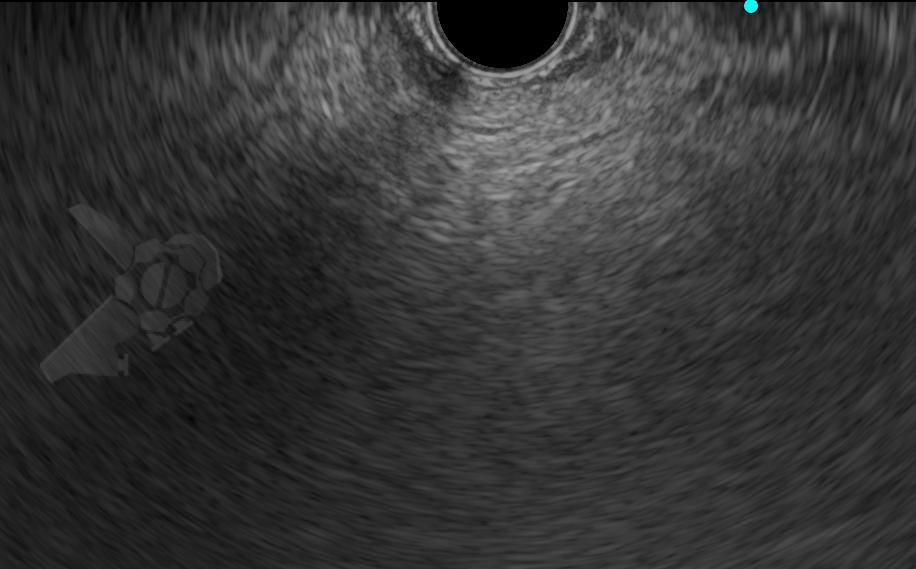

O diagnóstico no EUS se deu pela imagem pancreática hiperecoica difusa ou salteada, com borramento de seus limites e difícil caracterização do ducto pancreático principal ao invés do aspecto em “sal e pimenta” bem delimitado habitual – veja as imagens ilustrativas abaixo:

Imagens ilustrativas: